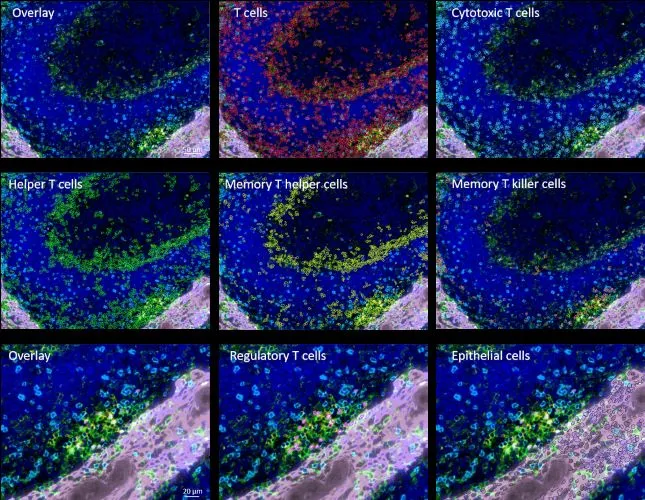

Investigating T-Cell Communities in Immune Tissues with StrataQuest 8

Multiplex fluorescence imaging of tonsil tissue analyzed in StrataQuest to quantify and map T-cell subsets within and around germinal centers.